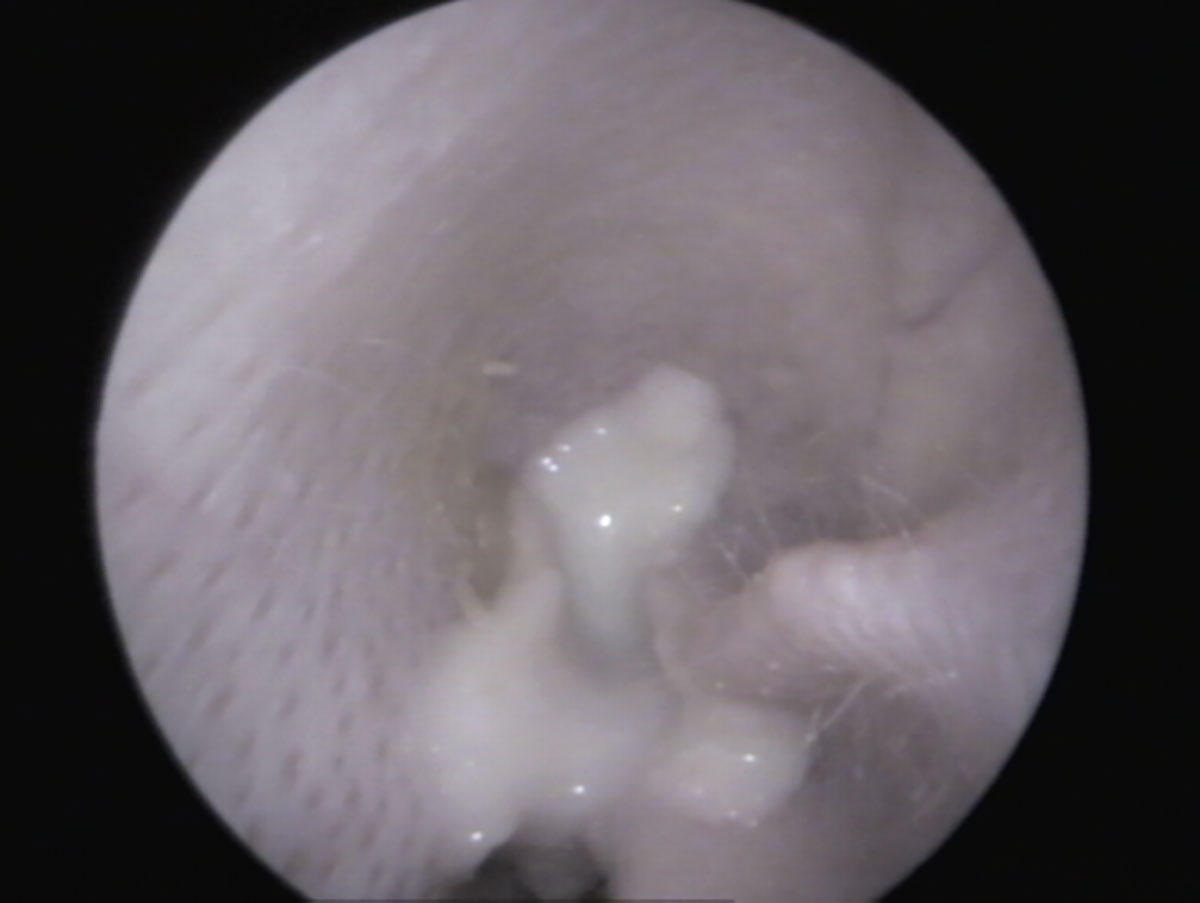

Fig. 4: Vista dell’orecchio esterno pieno di pus di un coniglio – l’orecchio esterno senza alterazioni suggerisce che il pus provenga dall’orecchio medio

Fonte: J. Hein

In un orecchio sano, tirando delicatamente il padiglione auricolare verso l’alto (Fig. 1), si riesce solitamente a vedere fino al timpano (Fig. 3). Se è presente materiale nel condotto uditivo, è importante distinguere se si tratta “solo” di cerume accumulato (bianco in profondità, giallastro verso l’orifizio) e il condotto uditivo è altrimenti normale, oppure se sono presenti segni di infiammazione (arrossamento, gonfiore, lesioni, liquefazione del secreto) (Fig. 4) e possibili cause primarie come corpi estranei e/o ectoparassiti.